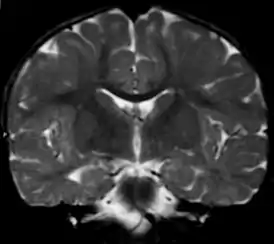

![]() Вид фронтального среза головного мозга при метахроматической лейкодистрофии (МРТ). | |